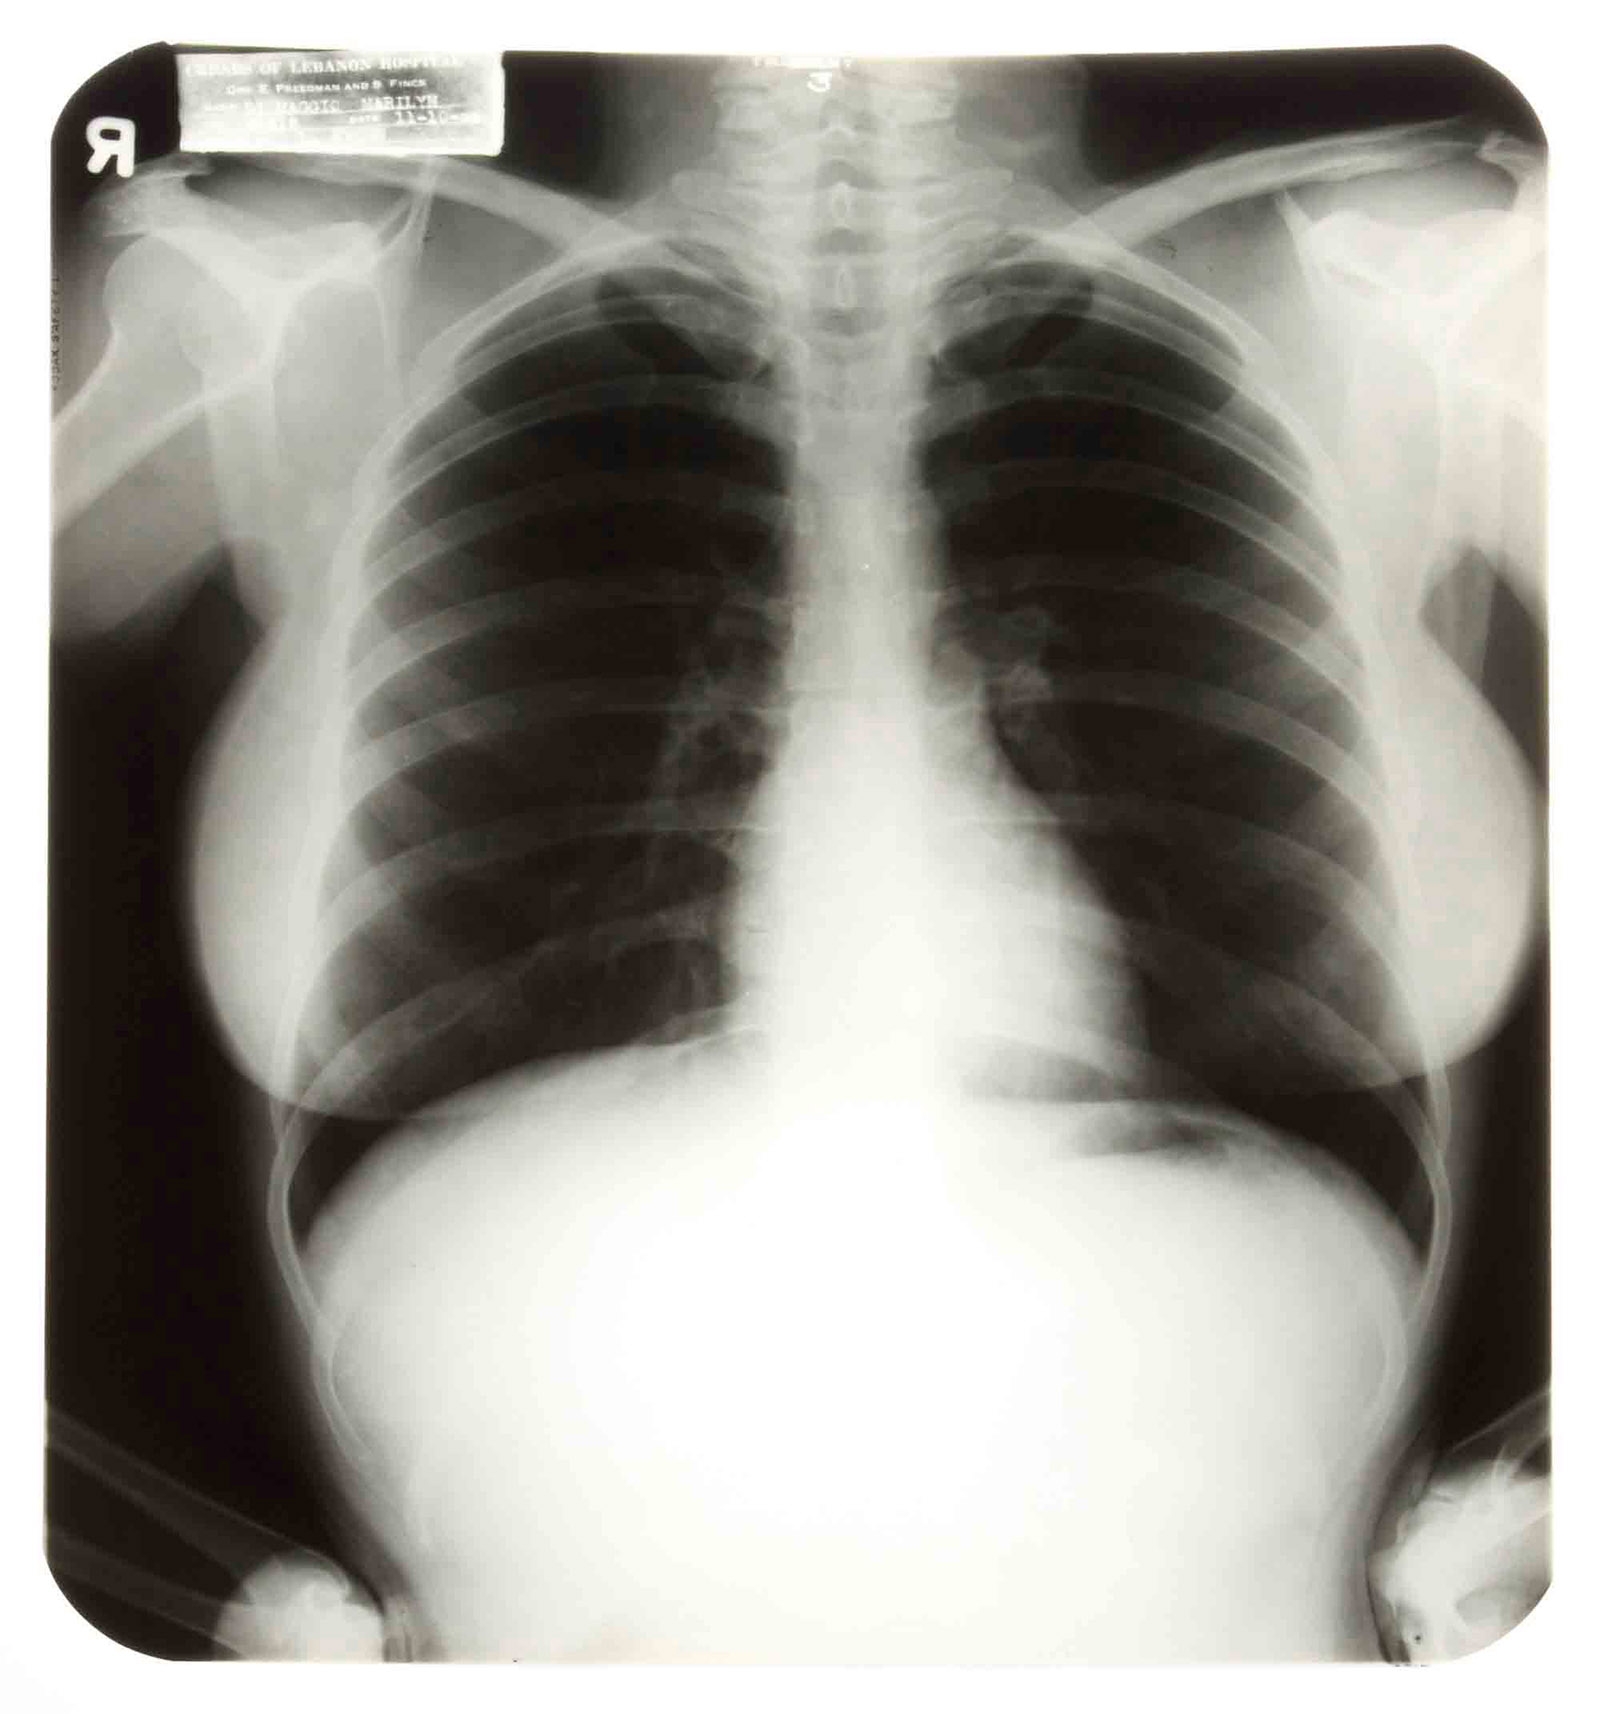

Por primera vez, un estudio numeroso demuestra que un fármaco que activa el sistema inmunológico podría mejorar la supervivencia en los pacientes del tipo más común de cáncer pulmonar.

El estudio sobre cáncer pulmonar puso a prueba Opdivo, de Bristol-Myers Squibb, que bloquea una proteína que impide al sistema inmunológico atacar las células cancerosas. Funcionó mejor que la quimioterapia para los pacientes con una variedad de cáncer pulmonar diagnosticada en más de 120 mil personas en Estados Unidos cada año.

Todo éxito en la lucha contra el cáncer pulmonar es bienvenido. Los pacientes suelen ser diagnosticados cuando la enfermedad ya está avanzada. Es el cáncer más mortífero en la nación. Unas 220.000 personas serán diagnosticadas este año y que unas 160.000 morirán, estima la Sociedad Oncológica Estadounidense.

En el nuevo estudio, unos 300 pacientes fueron asignados al azar para recibir infusiones de Opdivo o Docetaxel, un fármaco de quimioterapia, cada dos semanas. La tasa de supervivencia mediana fue de más de 12 meses para los primeros y unos 9 meses para los segundos. La diferencia parecería poco significativa, pero la supervivencia a largo plazo suele ser mínima para estos pacientes.

Los tumores se redujeron en casi el 20 por ciento de los pacientes de Opdivo en comparación con un 12 por ciento entre los demás.